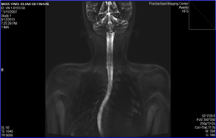

On August 17, 2015 we brought 30 pages of the MRI results from PRACHACHUEN IMAGINE CENTER CO. LTD which cost us about USD $1,000.00. We submitted the hard and soft copies to Doctor Sumroeng Neti. He downloaded everything to his PC and observed all the pages, as well as read the results, as we sat in his office. Afterward, he looked at us and said, “I have good news and bad news. We were quite shocked to hear the bad news and he continued; “the good news is she has no complications in relation to the “Idiopathic Scoliosis” and the bad news is the curve is 70 degree (which is contrary to the radiology result which stated that “The Cobb is about 54 degree, measured from T5 to L3” and he said she needs urgent surgery otherwise her curve will be bigger and she will become deformed.

Yael took X-rays every two months to be sent to Dr. Leonel (LA), in order to monitor know the status of the curve degree and improvement. With the passage of time following her rapid growth, the lower part of her spine has started a gradual curve till it could be observed as she dressed. Dr. Leonel suggested that the curve on her lower back needs to be corrected. Again, we started worrying about the second surgery despite Dr. Leonel informing us that it would be just correction, and not like the first one.

“Scoliosis is a three-dimensional deformity of the spine and trunk. Also it is a lateral curvature of the spine >13 degrees by Cobb method. The majority of scoliosis cases (80–90%) are adolescent idiopathic scoliosis (AIS). The remaining cases are of other origin (congenital, neuromuscular, mesenchyme disorders, connective tissues, and Degenerative (adult) and is associated with syndromes such as Mar fans.)”. (See diagrams/pictures on how to assess the scoliosis. source https://www.bspc.com.au/)

Please observe carefully the diagram to assess scoliosis for appropriate and earlier solutions. It is advisable for school-age kids to screen for scoliosis at school. Parents could assist by checking for early warning signs every six months. However, if one or more of these signs are present it does not necessarily mean scoliosis has developed so parents should consult their physicians.